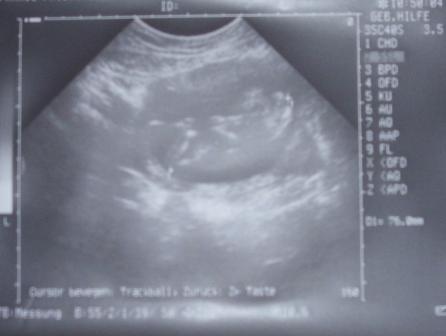

Hallo Mädels, heute war endlich der ersehnte FA Termin nach ewigen 4 Wochen... Hab 1 kg abgenommen (nicht schlimm, hab genug Reserve), mein Blutdruck war okay... Zwerglein ist ca. 8cm groß - die Ärztin meinte es ist mehr, weil es krumm da lag... und hing da wie in einer Hängematte, ab und zu die Beinchen rumbaumeln lassen Achso bei mir wurde über den Bauch geschallt... Dann hier noch ein Bildchen, es ist nur abfotografiert, man kann gut Kopf, Arm und Bein sehr gut erkennen... ich hoffe ihr erkennt´s auch trotz schlechter Qualität, hab´s nicht besser hingekriegt

Bild zu VU Bericht mit Foto - Forum für März - Mamis